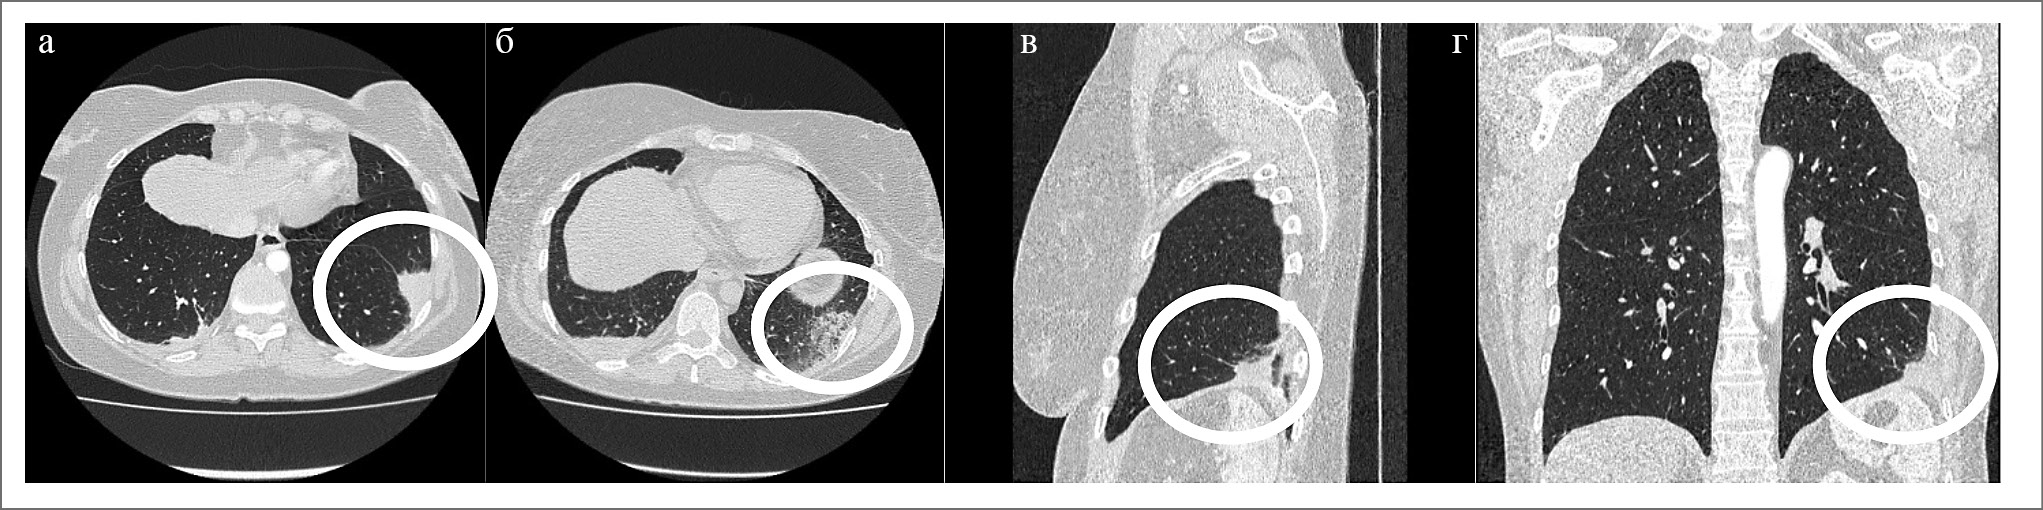

В коагулограмме: фибриноген 7,8 г/л, D-димер 1167 нг/мл (норма до 500 нг/мл), запланировано проведение компьютерной томографии (КТ). 30.09.2018 выполнена КТ органов грудной клетки (КТ ОГК) с контрастным усилением Омнипаком 50 мл с толщиной срезов 0,5–1,2 мм. В описании обращали на себя внимание единичные лимфоузлы средостения размерами 10×12 мм. В S9 нижней доли левого легкого описан субплеврально расположенный участок инфильтрации легочной ткани треугольной формы размером около 30×25×25 мм с фиброзным компонентом (рис. 1), плевропульмональными спайками. В кардиодиафрагмальных синусах – торакоабдоминальные липомы.

Рис. 1. КТ ОГК – субплевральная инфильтрация слева